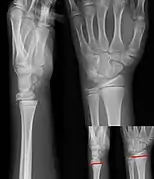

Salter–Harris fracture types

There are nine types of Salter–Harris fractures; types I to V were originally described,[3] and types VI to IX were added subsequently:[5]

• Type I – transverse fracture through the growth plate (also referred to as the "physis"):[6] 6% incidence

• Type II – A fracture through the growth plate and the metaphysis, sparing the epiphysis:[7] 75% incidence, takes approximately 12-90 weeks or more in the spine to heal.[8]

• Type III – A fracture through growth plate and epiphysis, sparing the metaphysis:[9] 8% incidence

• Type IV – A fracture through all three elements of the bone, the growth plate, metaphysis, and epiphysis:[10] 10% incidence

• Type V – A compression fracture of the growth plate (resulting in a decrease in the perceived space between the epiphysis and metaphysis on x-ray):[11] 1% incidence